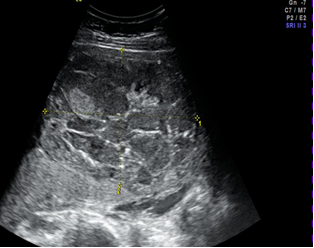

Abb. 7: Retroplacentares Hämatom und vorzeitige Placentalösung